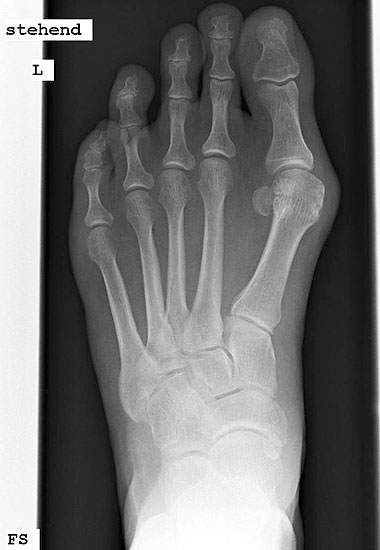

Röntgenaufnahme des Fußes im Stehen im dorsoplantaren und seitlichen Strahlengang (Abb. 1a-b).

Beurteilung des ersten Intermetatarsalwinkels (IMA), des Hallux valgus Winkels (HVA), des distalen (Distal Metatarsal Articular Angle, DMAA) und proximalen Gelenkflächenwinkels der Grundphalanx (Proximal Phalangeal Articular Angle, PPAA).

Abbildung 1a

Abbildung 1b

Direkt postoperativ Röntgenkontrolle (Fuß in zwei Ebenen). Sechs Wochen postoperative Röntgenverlaufskontrolle in zwei Ebenen im Stehen. Ist die Überbauung der Arthrodese nicht gut zu beurteilen, kann eine ergänzende 45° Supinationsaufnahme des Fußes angefertigt werden, die einen guten Einblick in das Tarsometatarsale-I-Gelenk ermöglicht.